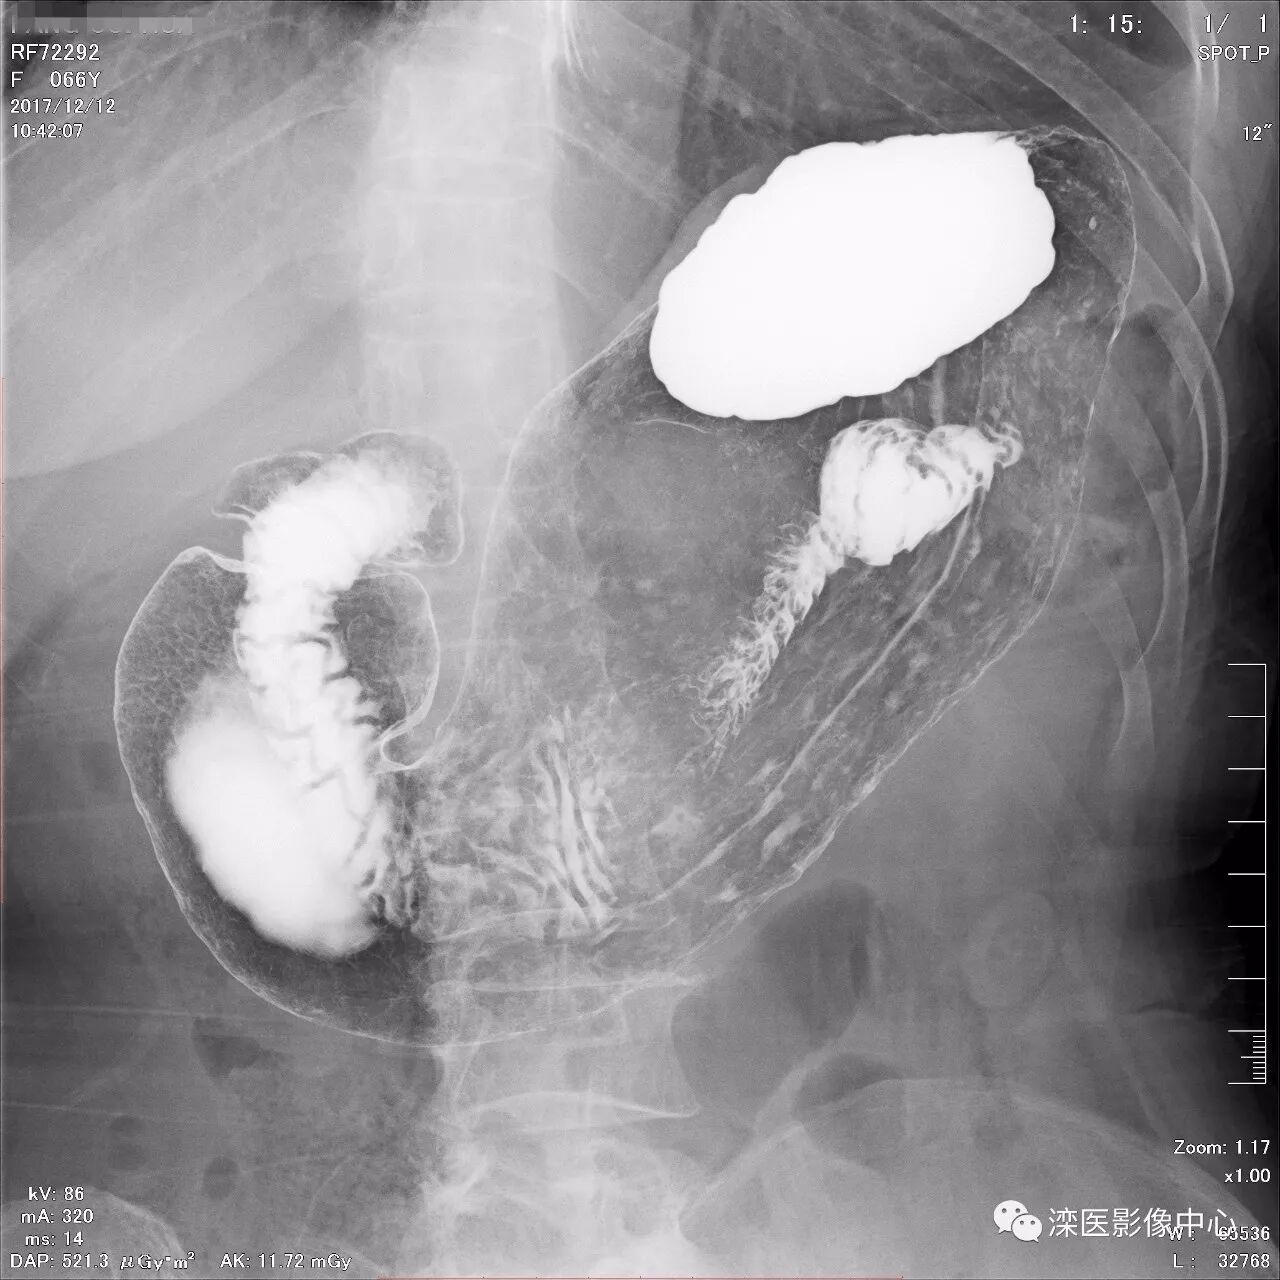

正位,显示食管、贲门及喉咽部的粘膜像)

(左前斜位,显示食管、贲门的粘膜像

(右前斜位,显示食管、贲门的粘膜像)

(以上图像是患者立位+卧位,通过变换体位,多角度显示了贲门胃底、胃体、胃大弯、胃小弯、胃窦、幽门及十二指肠球部、降部、水平部、升部的粘膜像和充盈像。本例患者女性,66岁,此次检查可以清晰显示胃小区结构,检查中发现患有慢性胃炎、胃下垂、十二指肠降部憩室)